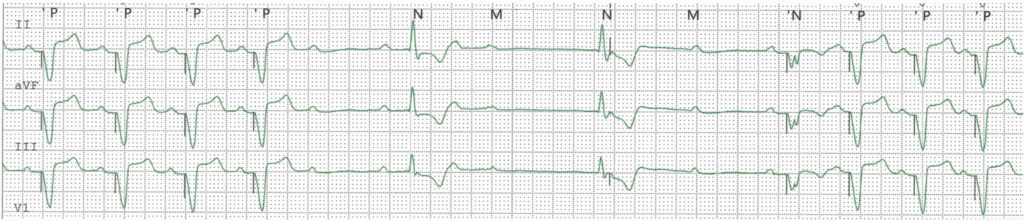

A 72-year-old patient was admitted for stroke. He had been implanted with a dual-chamber pacemaker 2 months ago for sinus dysfunction. Interrogation of the pacemaker was normal and did not disclose any atrial arrhythmias that may have explained the neurological event. A chest X-ray was performed and is shown

The ventricular lead is in the LV via a patent foramen ovale

• The PA view the ventricular lead would be expected in a lower position

• The lateral view shows the V lead to be posterior, whereas an RV lead would be anteriorly located.

• LV capture results in a negative QRS in lead I (which may be observed occasionally also with RV pacing) and an RBBB QRS morphology.